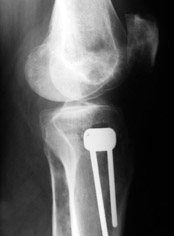

Большая просьба прокомментировать прилагавшиеся снимки. Видно, что сделано что-то красивое, но не совсем понятно, по какому поводу, как рассчитывалась коррекция, и что именно сделано.

Поводом для проведения всех корригирующих остеотомий у исследуемых пациентов служил гонартроз 1-3 стадии, косметическая коррекция в большинстве случаев являлась вторичной.

Хотя любого больного она не в меньшей степени интересовала. При всех видах остеотомий обязательным требованием являлась восстановление баланса пассивных и динамических сил путем восстановления оси конечности, стабильности связочного аппарата и контроля над мышечной активностью при осевой нагрузке. Как правило, учитывалась сохранность гиалинового хряща на компенсирующем нагрузку мыщелке бедра или большеберцовой кости. Предоперационное планирование осуществляли с поднагрузочных рентгенограмм обоих конечностей.

Дополнительными методами диагностики являлось измерение внутрикостного давления в зоне гипернагрузки и радионуклидные исследования нуклидами технеция. Применялись различные варианты остеотомий на различных сегментах. Для коррекции варусной-торсионной деформации:

высокие плюс, минус остеотомии большеберцовой кости,косая остеотомия малоберцовой. Для коррекции вальгусной деформации применялась плюс, минус надмыщелковая остеотомия бедренной кости. Фиксацию при высокой подмыщелковой остеотомии производили уникальной клинковой пластиной и тяговыми кортикальными винтами. Угол коррекции выставлялся

специальным угломером и направителем.